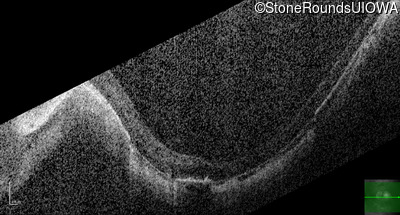

Optical Coherence Tomography - Right - 10/300

Exemplar / OCT Stack

OCT Stack